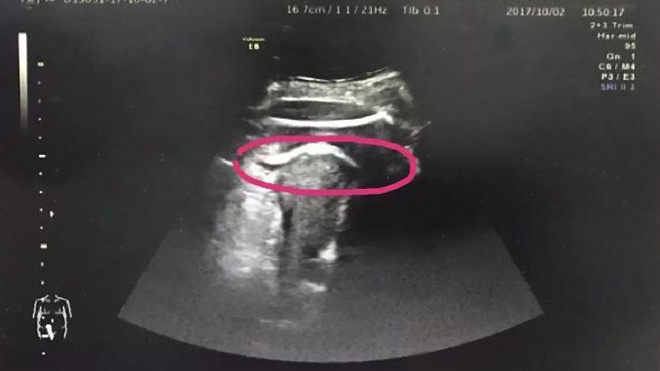

Kết quả siêu âm cho thấy chân của thai nhi đã xuyên qua thành tử cung, thò sang khoang bụng và đùi bị mắc kẹt tại thành tử cung. Nhận thấy tình hình quá nghiêm trọng, sản phụ đang đối mặt với nguy cơ bị nhiễm trùng, xuất huyết còn con dễ bị ngạt khí nên các bác sĩ đã nhanh chóng đưa chị Trương qua phòng mổ.

Vùng khoanh màu hồng là chân đứa trẻ đạp thủng tử cung.